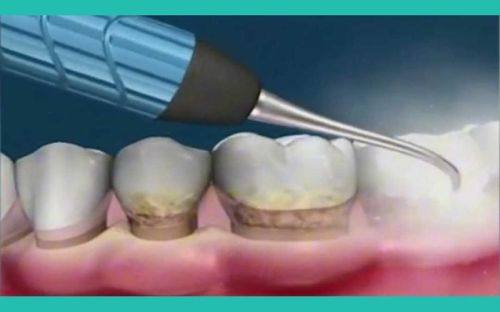

牙周与疑难病例诊疗:可开展牙周病手术治疗,同时能处理各类口腔疑难病例,为复杂口腔问题提供全方面的解决方案。

擅长牙周病手术治疗与根管治疗,能够有效解决牙周炎症、牙髓病变等问题,同时可处理各类口腔疑难杂症,为患者提供全方面的口腔诊疗服务。

“我牙周炎好几年了,牙龈经常出血,牙齿也有点松动,找田医生做了牙周刮治和手术治疗,现在牙龈不再出血,牙齿也稳固了特别多。田医生态度特别好,会耐心回答我的各种问题,整个治疗过程都特别放松,没有什么痛苦。”